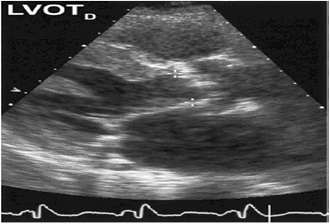

• Misura il rapporto tra velocità registrate nel LVOT ed all’orifizio aortico

Immagine41.jpg